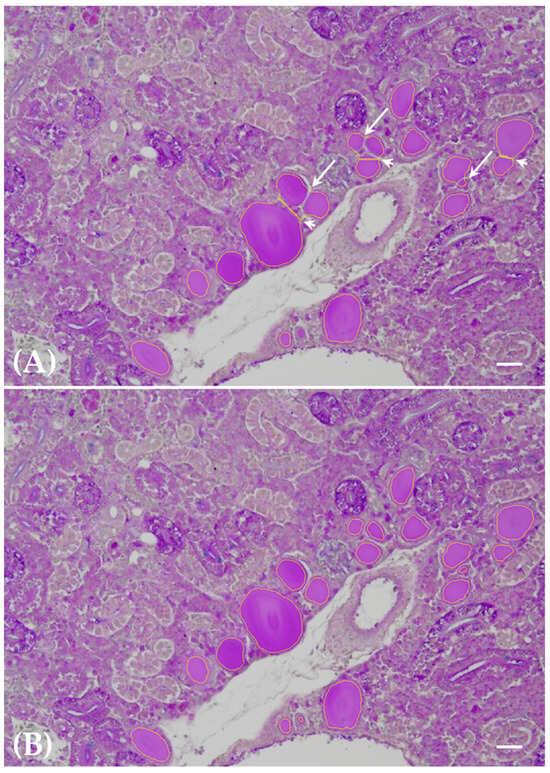

3.2. Thyroid Follicle Colloid Segmentation